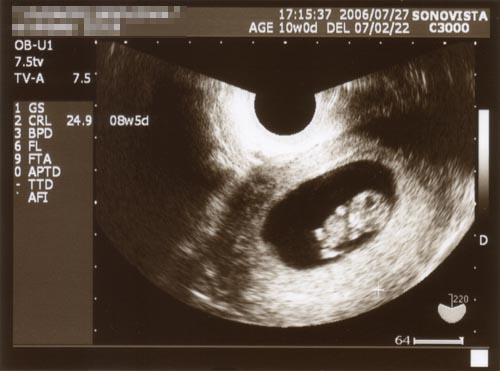

●2006.07.28(Sat)

恒例の検診報告です(笑)

今回も随分大きくなってました。

![]()

(クリックすると拡大します)

頭腎長は24.9mm。たった2週間で1.5倍も!大きくなってます。

今日はモゾモゾと手足を動かしていたそうです。

そして出産予定日が決定しました!

なんと!

3月3日(土)

ひなまつり!?

なんとまあ、運命というか、偶然というか。

3月3日といえば、結婚する1年前、妻の実家へご挨拶に伺った日でした。

いわゆる「娘さんをください」というやつです。

あの日からちょうど5年後にこどもが生まれるとは・・・。

次の検診までには母子手帳をもらってくるように言われ、

いよいよマタニティが本格化してゆきます。

夫の私にできることを色々と考えてゆかなくてはなりませんね。